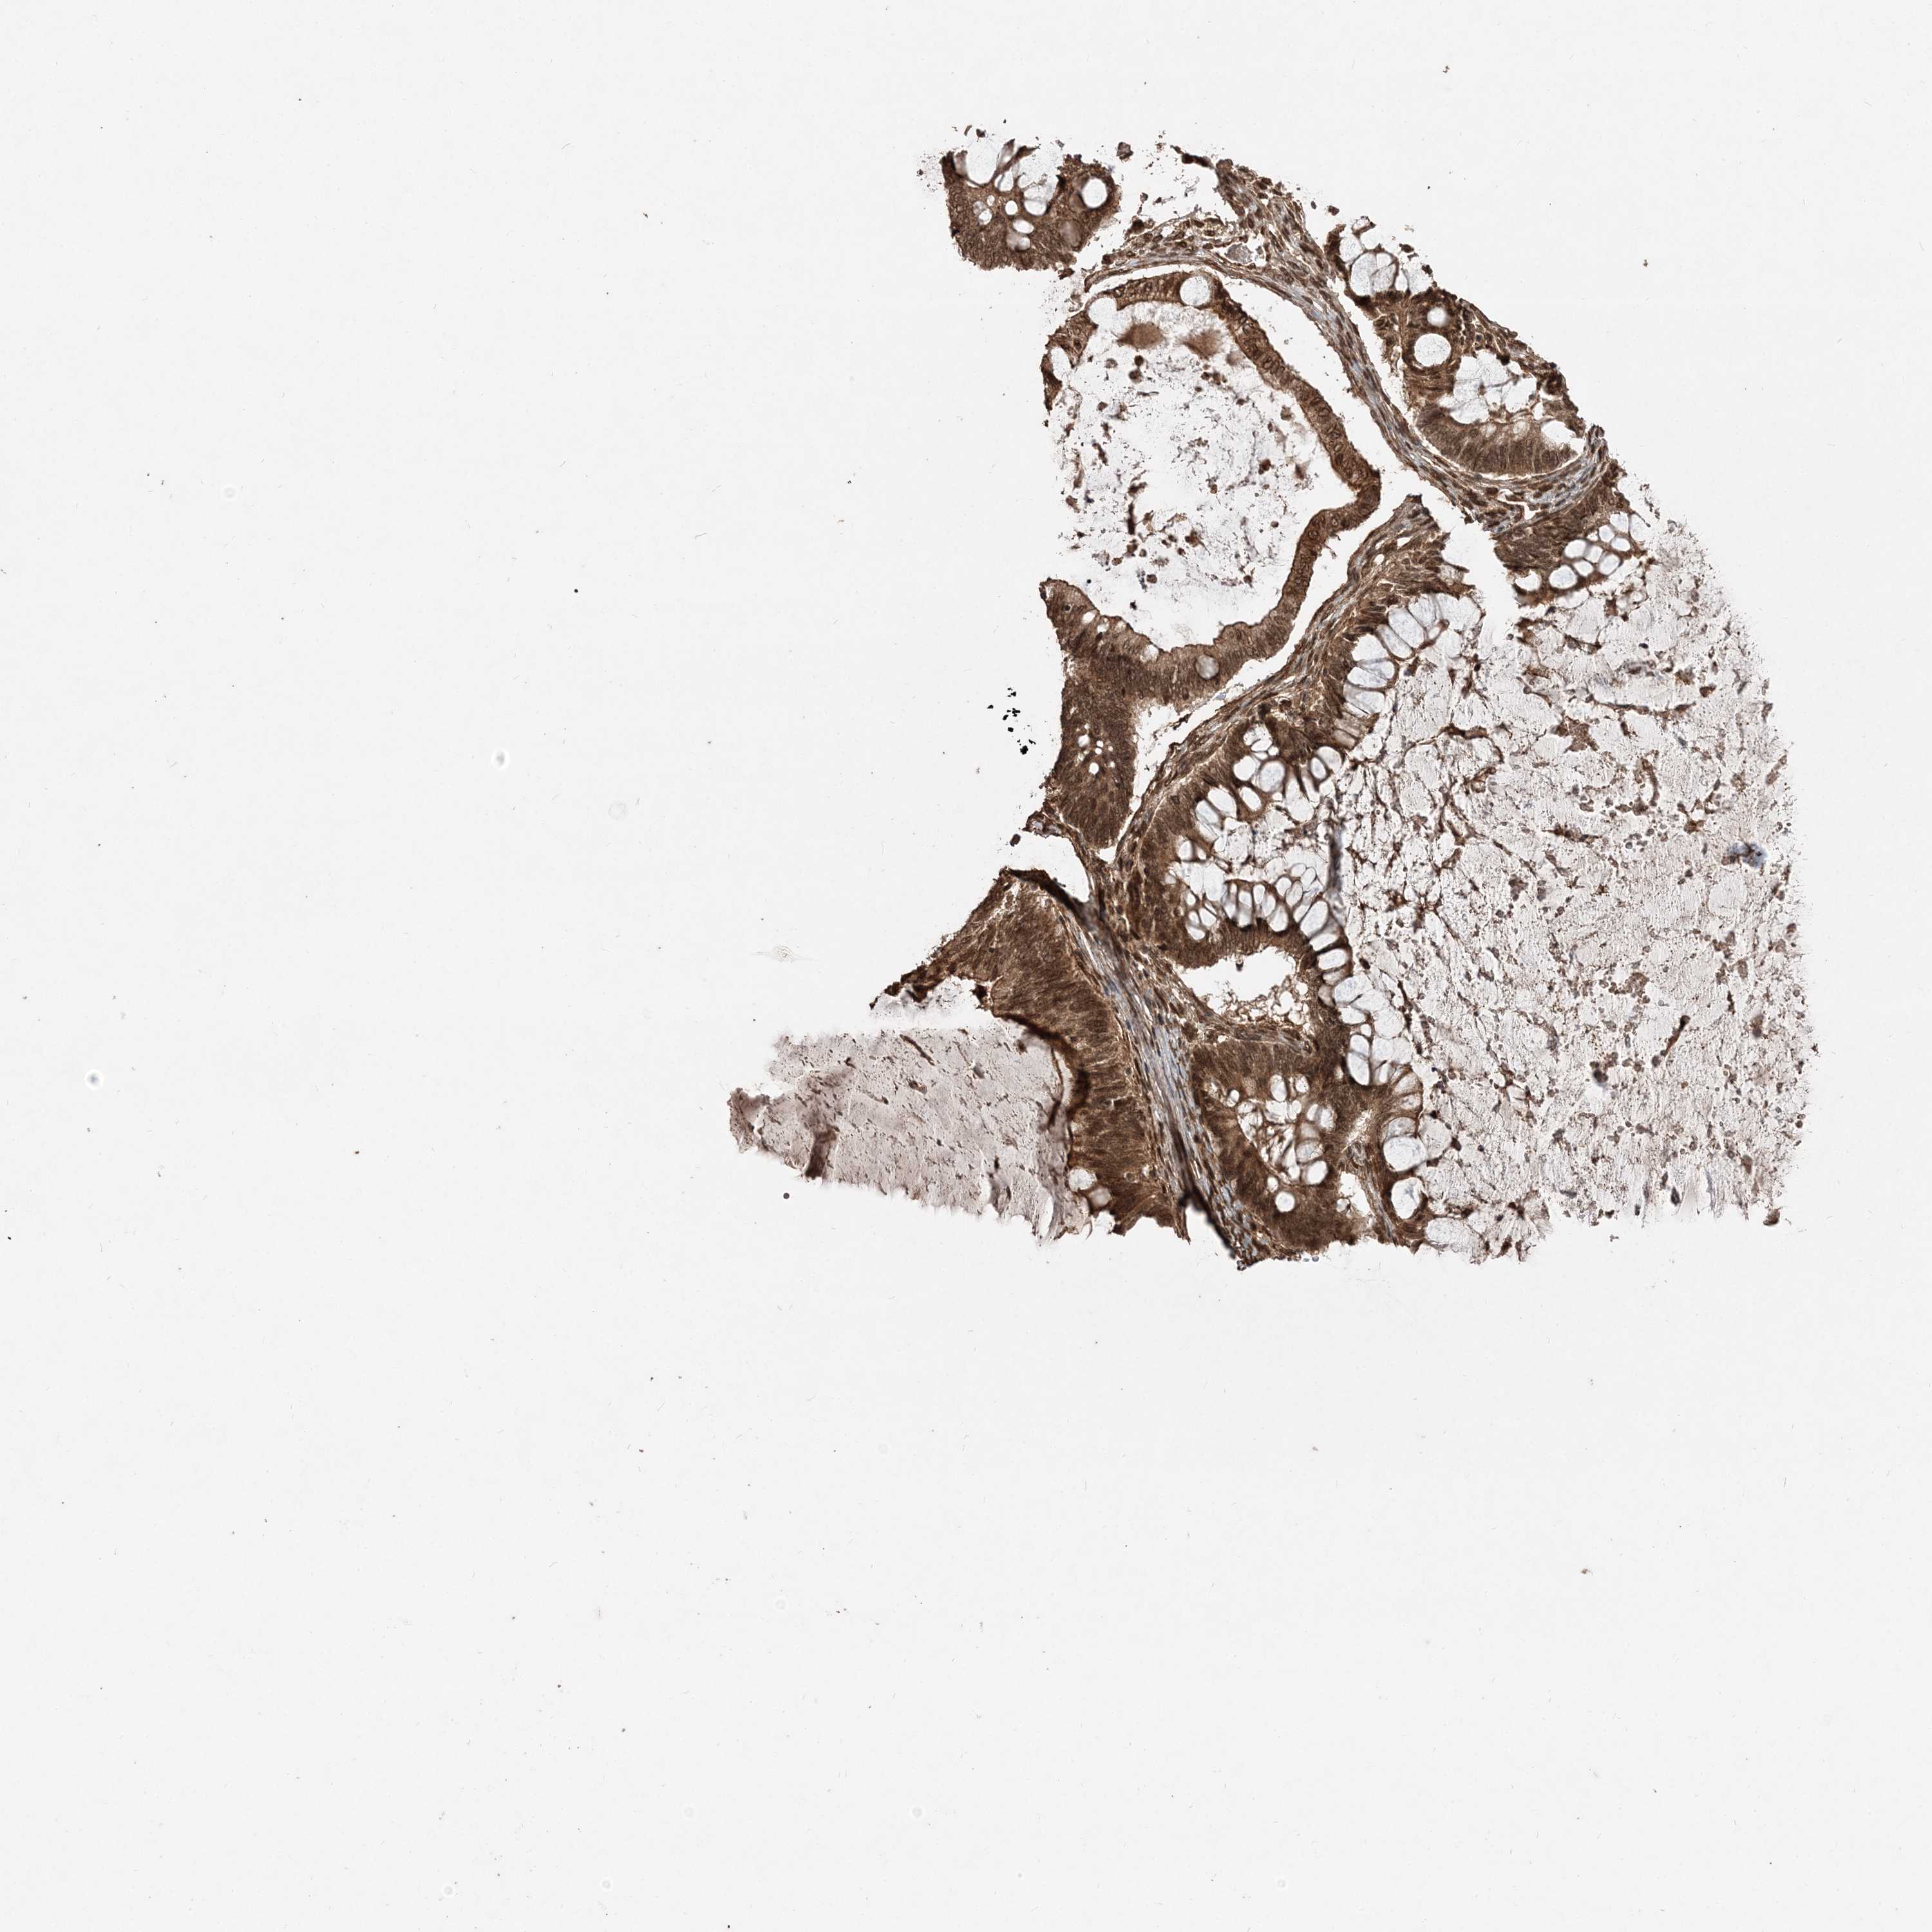

OVARIAN CANCER - Protein expressioni

A mouse-over function shows sample information and annotation data. Click on an image to view it in a full screen mode. Samples can be filtered based on level of antibody staining by selecting one or several of the following categories: high, medium, low and not detected. The assay and annotation is described here.

Note that samples used for immunohistochemistry by the Human Protein Atlas do not correspond to samples in the TCGA dataset.

Antibody stainingi

Antibody staining in the annotated cell types in the current human tissue is reported as not detected, low, medium, or high, based on conventional immunohistochemistry profiling in selected tissues. This score is based on the combination of the staining intensity and fraction of stained cells.

Each image is clickable and will lead to virtual microscopy that enables deeper exploration of all samples and also displays staining intensity scores, fraction scores and subcellular localization as well as patient and tissue information for each sample.

Antibody HPA035048

Antibody HPA035049

Cystadenocarcinoma, serous, NOS

Carcinoma, endometroid

Cystadenocarcinoma, mucinous, NOS

Carcinoma, NOS